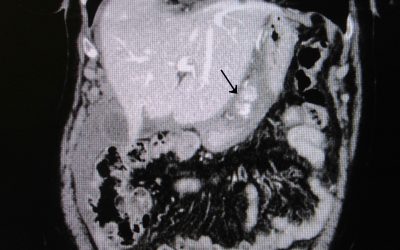

Un caso di rottura idiopatica dell’arcata arteriosa della piccola curvatura gastrica

di Enrico Ganz E’ riportato un caso di rottura spontanea dell’arcata vascolare della piccola curva gastrica in adiacenza dell’antro. Si discute successivamente il caso in rapporto alle conoscenze relative alle emorragie non traumatiche delle arterie gastriche....